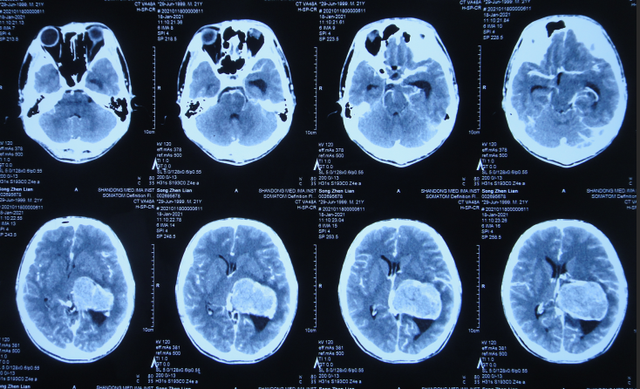

2021年3月8日(左颞角脑室腹壁外引流术后28天),进行了脑脓肿切除术(图-20)。

图-20:2021年3月8日头颅CT

2021年3月9日(左颞角脑室腹壁外引流术后29天,脑脓肿切除术后次日),查头颅CT示脑脓肿切除术后(图-21)。

图-21:2021年3月9日头颅CT

2021年3月12日(左颞角脑室腹壁外引流术后32天,脑脓肿切除术后5天),查头颅CT示仍有少量水肿(图-23)。

图-23:2021年3月12日头颅CT

但拔除引流管后11天即2021年4月6日,患者出现头痛,查头颅CT示颞角扩张(图-24)。

图-24:2021年4月6日头颅CT

因此于2021年4月8日,进行了脑室腹腔分流术;术后身体一切正常(图-25)。

出院后5个月即2021年9月中旬,出现偶尔头痛的症状,因此于出院后7个月后即2021年11月10日,第2次来到李小勇脑脊液科;入院时:时有头痛(图-26),身体其他正常;查头颅CT示左侧颞角扩张(图-27)。

图-27:入院时头颅CT

入院后2天即2021年11月12日,给予了颞角分流管调整术;术后第2天查头颅CT示颞角仍扩张(图-28)。

图-28:2021年11月14日头颅CT

入院治疗14天即2021年11月24日,查头颅CT示颞角缩小(图-29),患者头痛基本消失(图-30)。

图-29:2021年11月24日头颅CT